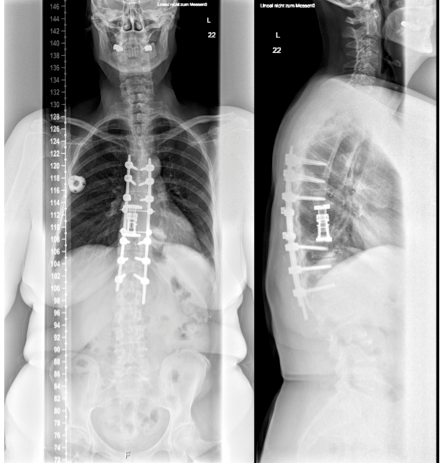

A 59-year-old woman presented with persistent pain in the thoracic spine after low energy trauma 6 weeks ago. X-ray imaging showed vertebra compression fracture of Th9 with kyphosis of 20°. The patient had a history of three strokes, 15 and 13 years ago, with residual paralysis on the right side. She did not report of new neurological disability after trauma: no new motor dysfunction, no long tract signs, neither bladder nor bowel dysfunction. There was no history of malignancy in her family. MRI studies revealed a solid mass of 16x14x12 cm in the inferior posterior mediastinum on the left side with infiltration of Th9 and Th10 vertebral body and spinal canal infiltration with myelon compression (Figure 1 [Fig. 1], Figure 2 [Fig. 2]). Staging procedure including total spine MRI, abdominal and chest computed tomography (CT), cranial CT, and PET CT did not show distant metastasis. The interdisciplinary tumor board decided to perform a transthoracic needle aspiration biopsy first. The histopathological examination could not define a clear diagnosis. Therefore an open biopsy was performed. This result was not clear, too. At last, pleomorphic rhabdomyosarcoma or liposarcoma with rhabdomyogenic dedifferentiation were discussed. The proliferation index Ki67 was 70%, meaning high-grade sarcoma. Trimodality treatment was proposed: surgery with “en-bloc” resection followed by adjuvant multidrug chemotherapy and radiation beam therapy. The day after biopsy, the patient suddenly developed an ascending sensory spinal cord injury. We decided for a two-stage surgery, starting with immediate posterior decompression and stabilization: We performed a posterior decompression with complete resection of the posterior parts of the Th9 and Th10 vertebra with spinal canal clearance. Long segment stabilization was performed three levels above and three levels below (Figure 3 [Fig. 3]). After a few days of recovery the anterior procedure followed (Figure 4 [Fig. 4]). Via thoracolumbophrenotomy an “en bloc” resection including TH9 and Th10 vertebral body as well as 2 level cage reconstruction of the anterior column was performed (Figure 5 [Fig. 5], Figure 6 [Fig. 6]). The patient recovered quite well after surgery: no problems of wound healing, no new neurological deficits, sensory deficit improved. Adjuvant chemotherapy started 4 weeks after surgery with the first of 3 cycles in a 21 days period. Unfortunately chemotherapy had to be reduced and later stopped due to major side effects. A radiation beam therapy with total radiation dose of 60 Gy followed. The patient did well at 3 month and 6 month follow-up, showing no new neurological deficits, less pain. MR imaging after 6 month did not show local recurrence and PET CT did show no proof of relapse.

Figure 5: Postoperative X-ray (a.p. and lateral view). Posterior long segment pedicle screw stabilization and anterior reconstruction via expandable cage.